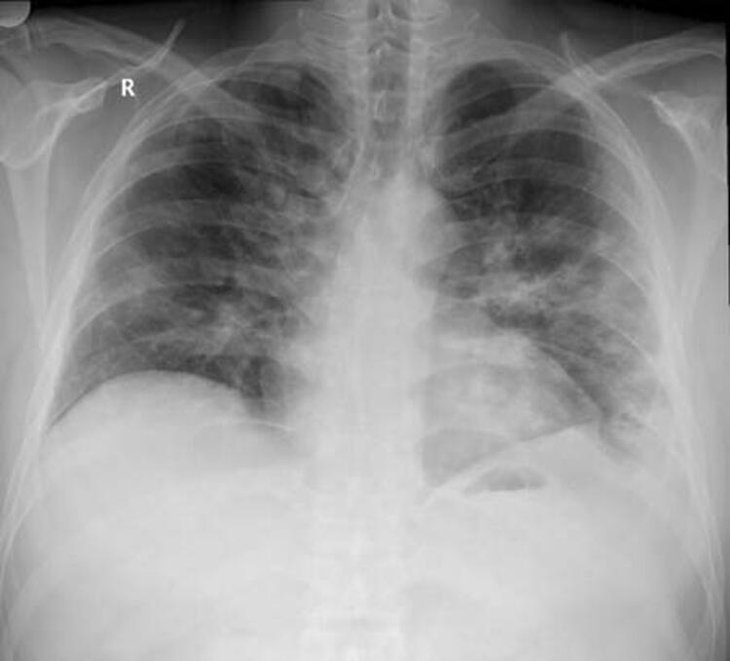

Ankara Şehir Hastanesinde koronavirüs tedavisi gören hastalara ait akciğer görüntülerine ulaştı. Görüntülerde, hastalığın ne kadar hızlı ilerlediği ve akciğerleri nasıl tuttuğu ortaya çıktı.

Prof. Dr. Karalezli, koronavirüs tedavisi gören hastalara ait akciğer görüntülerinden hastalığın yol açtığı tahribatı ve hastalar üzerindeki etkileri anlattı.

Tedavisine rağmen nefes darlığı şikayetleri devam eden bir hastaya uygulanan akciğer görüntülemesinde hastanın her iki akciğerinin büyük bir bölümünü enfeksiyon kapladığını tespit ettiklerini ifade eden Karalezli, "Bu hastalığın sonunun ne olduğunu bilmiyoruz. Akciğer tutulumları, bu şekilde olduğu zaman hastaları oksijen tedavisi ile gönderiyoruz."